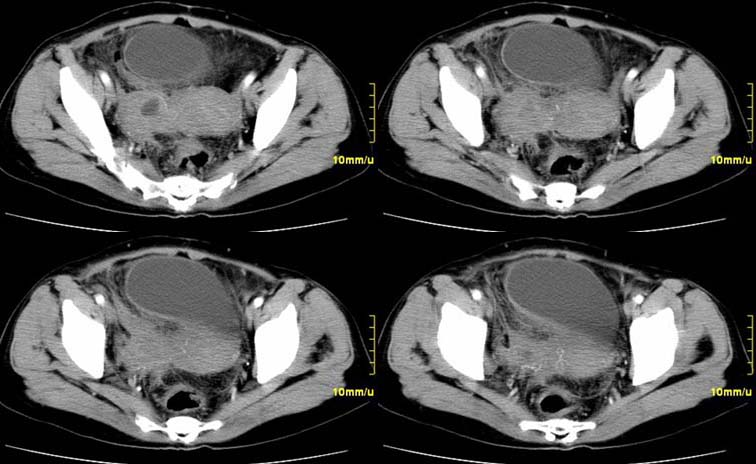

患者,52,右下腹疼痛一月,当时有发热,抗炎治疗20余天,至今仍疼痛,且有低热。

右附件区软组织包块,内囊变坏死,边缘模糊,与子宫,与膀胱分界不清,增强强化与子宫密度相近.盆腔内无肿大淋巴结考虑炎性包块可能性大。

右附件区软组织包块,内可见坏死,边界不清,周围软组织及脂肪组织可见密度增高,膀胱右侧壁增厚,并且呈膨胀不全的改变,考虑炎性包裹,不知道有没有手术史??

右侧附件见一肿块,边缘与周围组织分界不清,增强扫描见肿块明显强化,越到后期强化越明显,中央见坏死,内壁光整,与临近子宫壁、直肠及膀胱后壁均见炎症波及。这种厚壁肿块、内缘光整外缘模糊、增强扫描强化越后越强是附件脓肿典型的ct表现。

右侧卵巢输卵管慢性脓肿,炎症波及临近子宫、直肠及膀胱形成粘连。